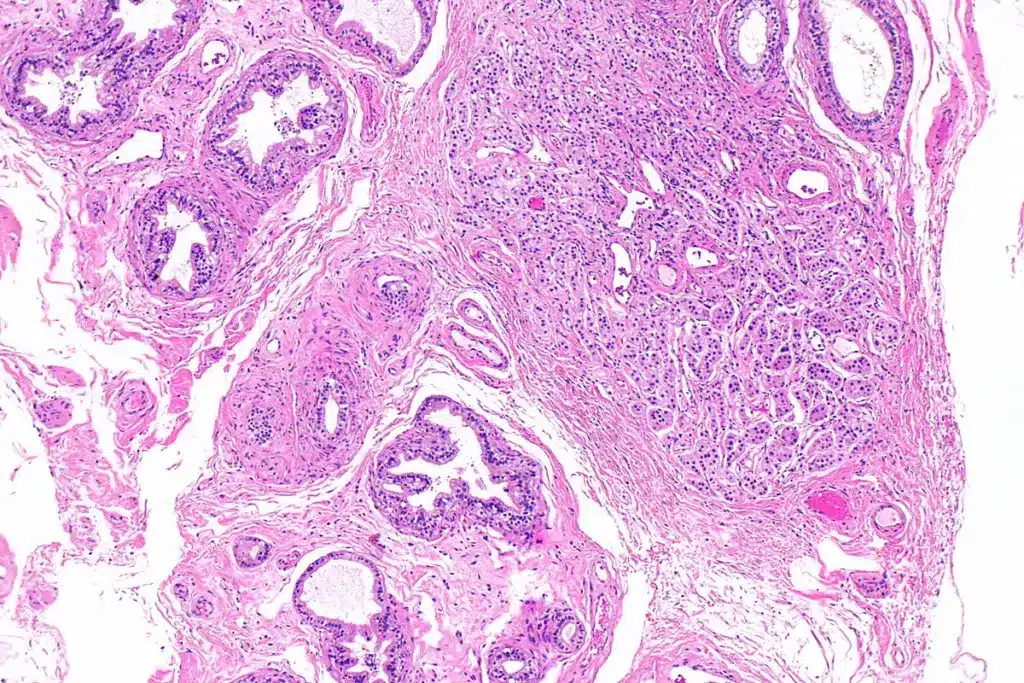

Definition and Prevalence of Squamous Cell Carcinoma

Squamous cell carcinoma starts in the squamous cells of the lungs. These cells line the airways. It’s mostly found in smokers or those who used to smoke. Studies show it makes up about 25-30% of lung cancer cases, making it a key part of NSCLC.

Distinguishing Features from Other Lung Cancer Types

Squamous cell carcinoma is different from other lung cancers like adenocarcinoma and small cell lung cancer. It grows in the center of the lung, causing symptoms like coughing and breathing trouble. Its location and growth can affect how it spreads, including to the brain.